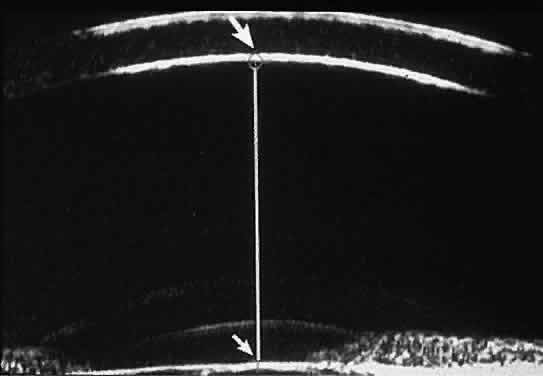

of the angle. In open-angle glaucoma, UBM can be used to measure the anterior chamber

angle in degrees, to assess the configuration of the peripheral iris, and

to evaluate the trabecular meshwork (Fig. 9).2,4 The angle configuration can be graded and compared with gonioscopic findings. In

is hazy or opaque.  Fig. 9. Angle configuration in eyes with open-angle glaucoma. A. Wide open angle with flat iris plane (D40r configuration by Spaeth gonioscopic

grading system). B. Moderately wide angle with anteriorly bowed iris plane (C30r by Spaeth

gonioscopic grading system). Fig. 9. Angle configuration in eyes with open-angle glaucoma. A. Wide open angle with flat iris plane (D40r configuration by Spaeth gonioscopic

grading system). B. Moderately wide angle with anteriorly bowed iris plane (C30r by Spaeth

gonioscopic grading system).